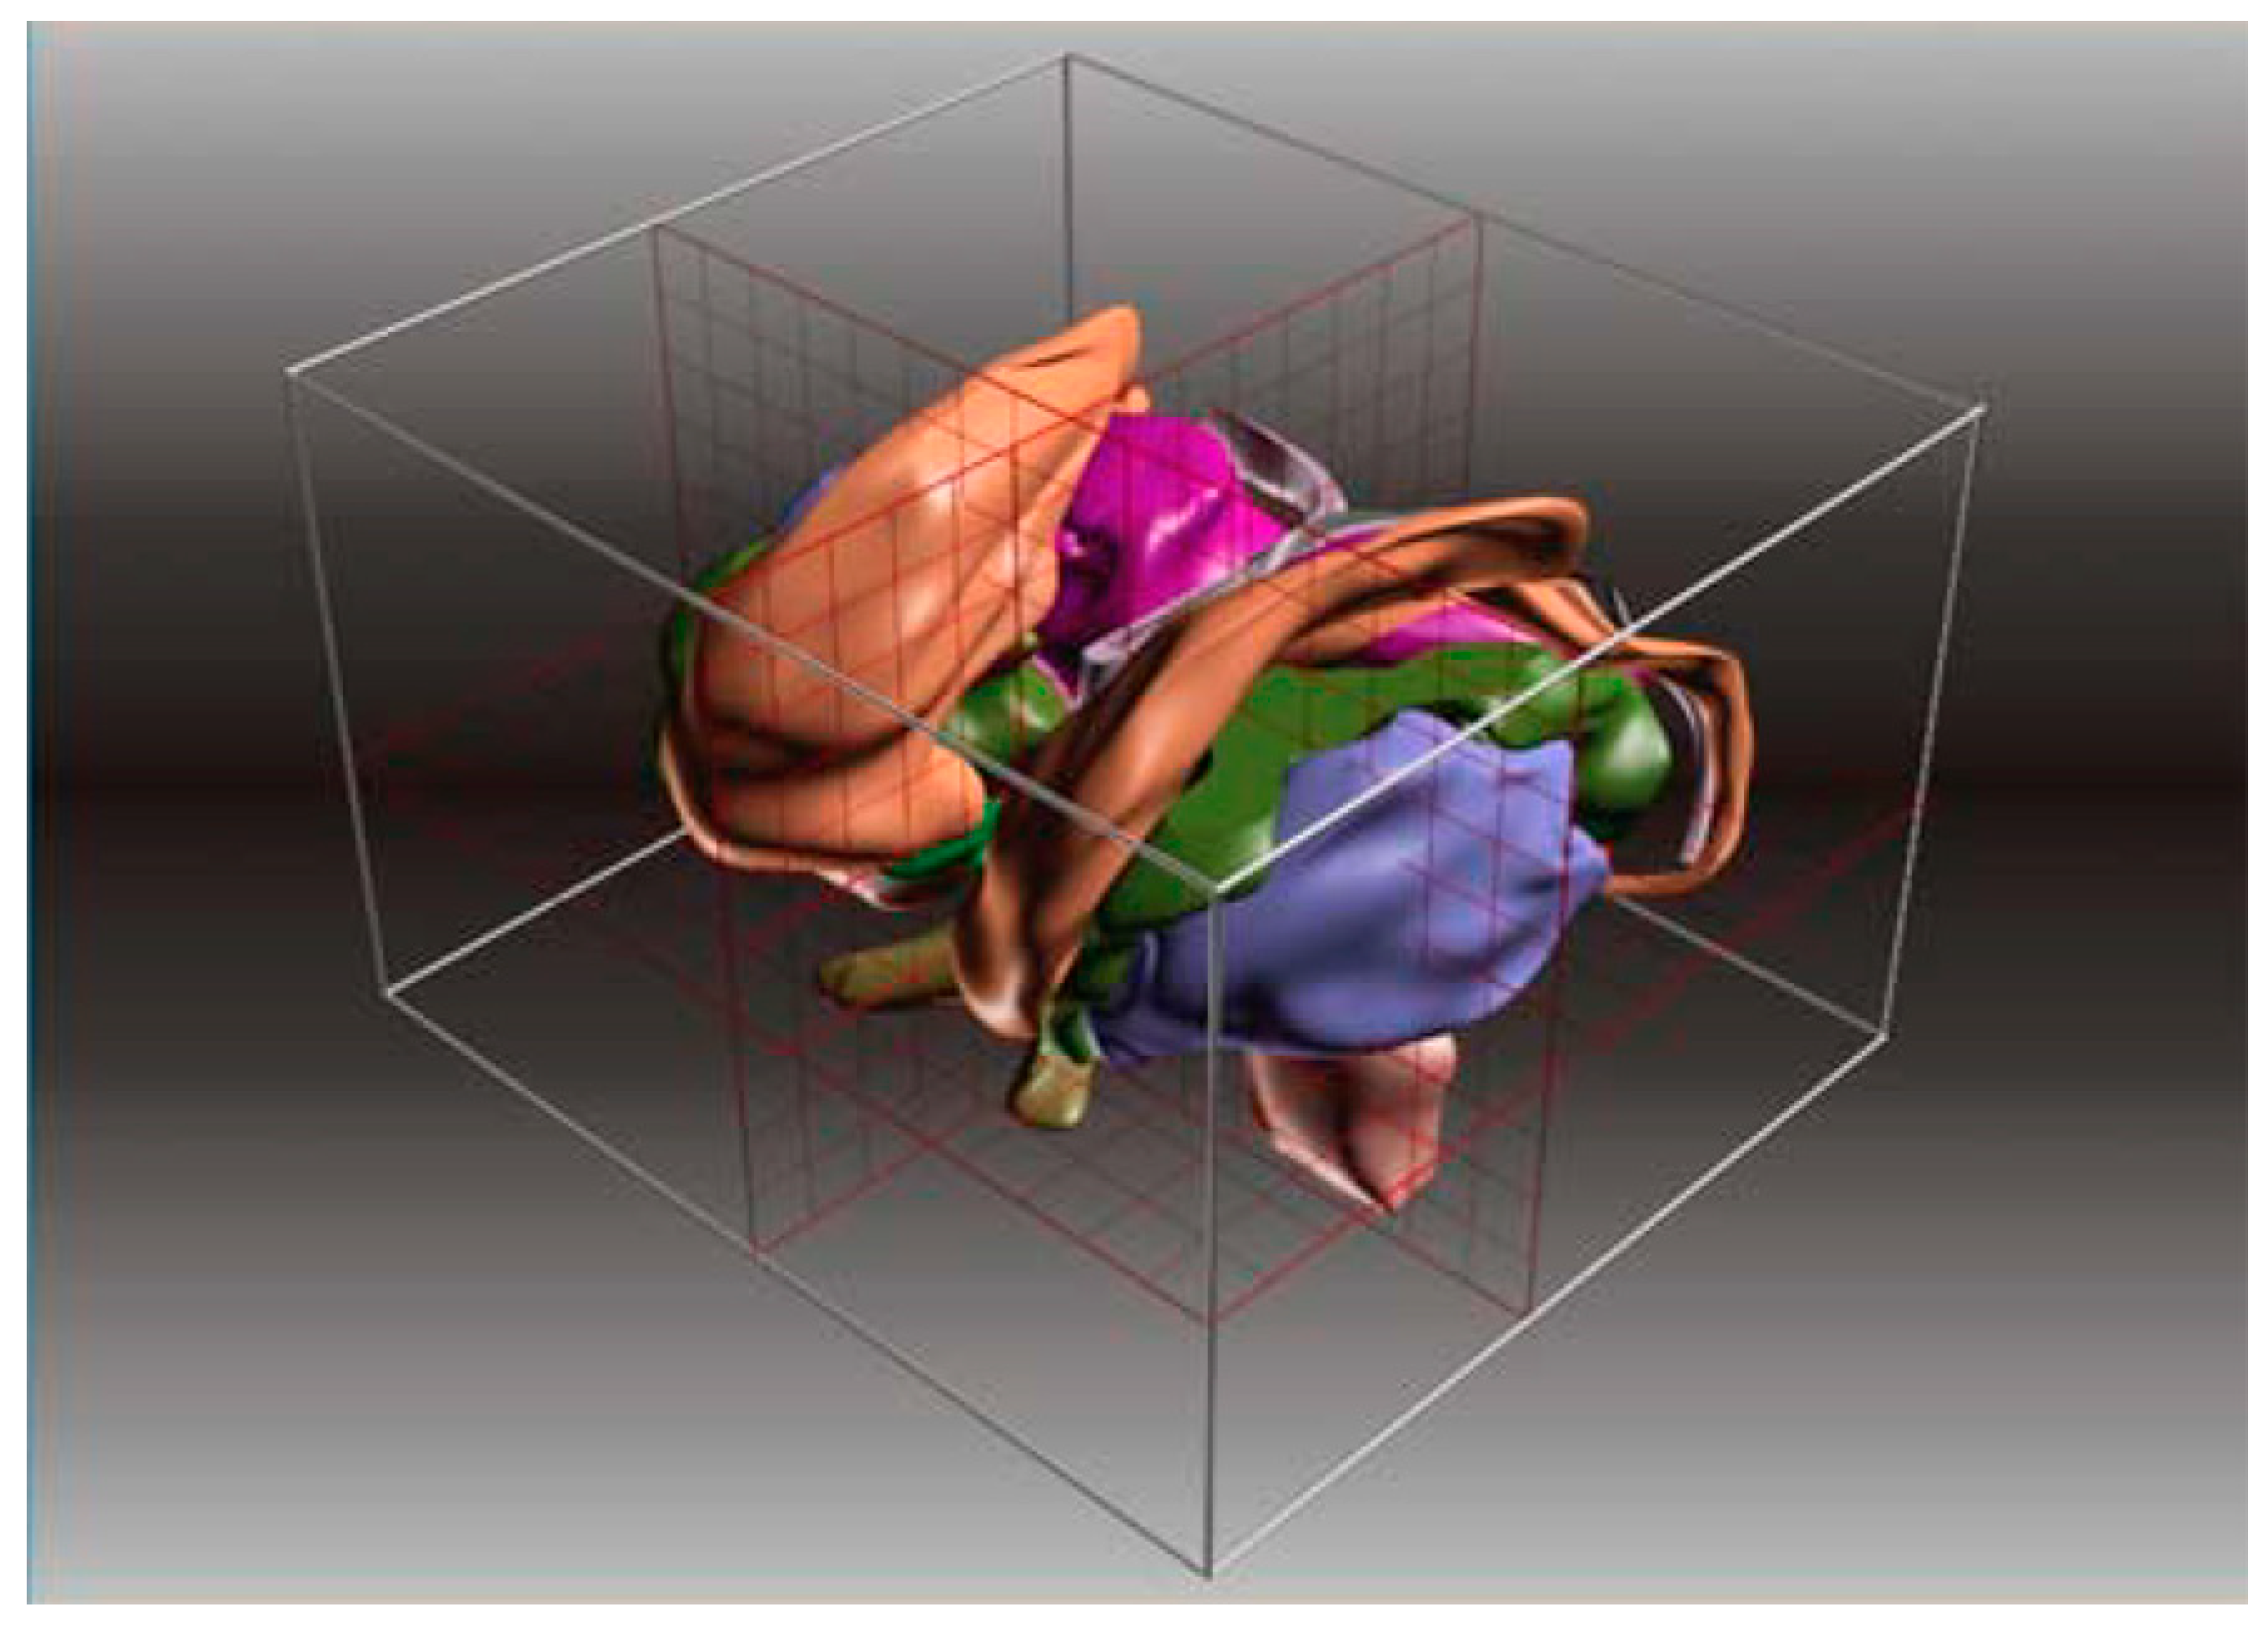

10. Three-Dimensional Rendered Atlases from Histological Sections and Multiatlas Collections